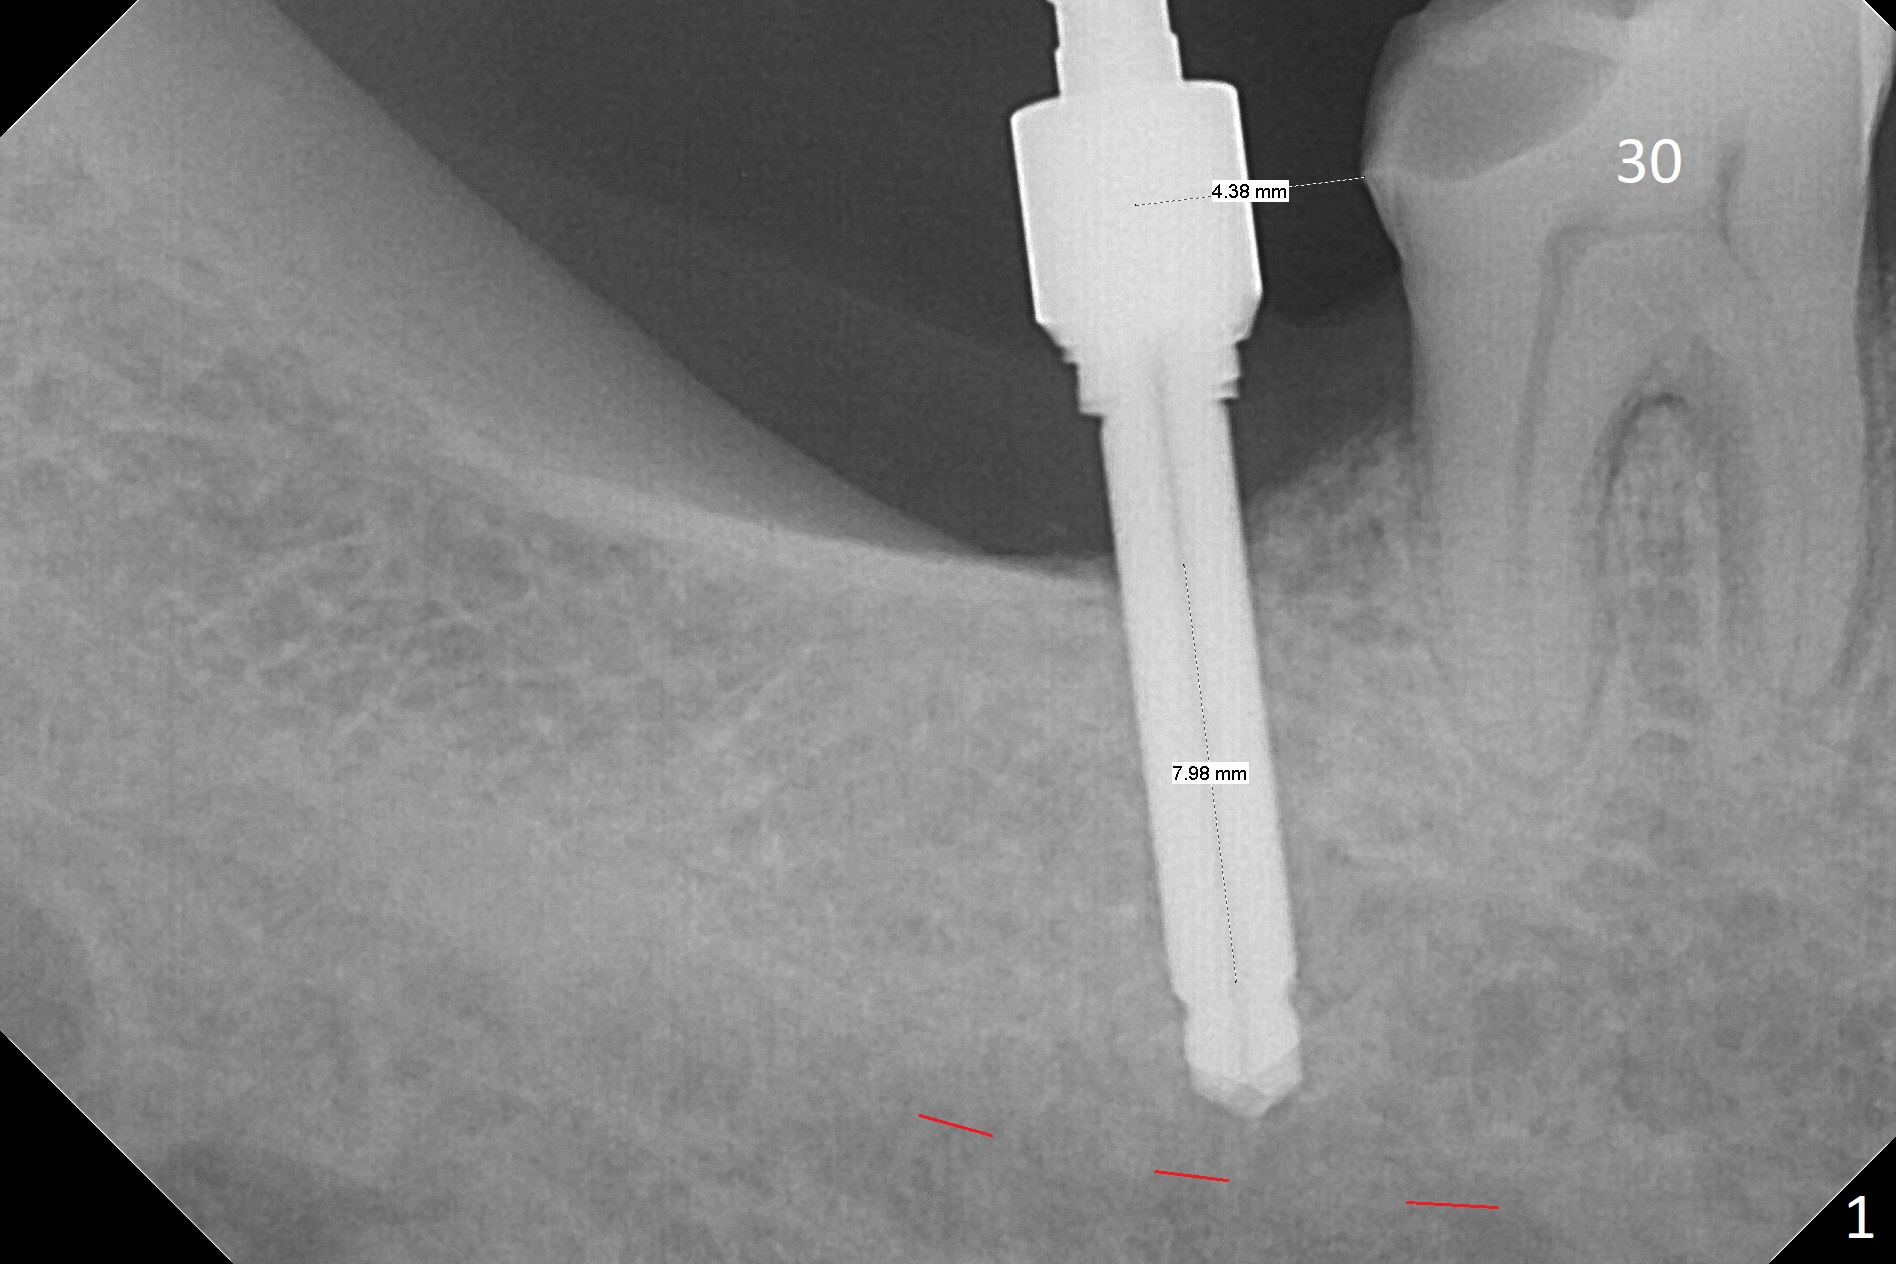

The ridge at #31 is wide buccolingually, but uneven with buccal lower. When a 3 mm drill reaches 13 mm in depth (Fig.1 (gingival level, flapless with Magic Split)), the patient feels pain with the osteotomy close to the Inferior Alveolar Canal (red dashed line). Subsequent osteotomy depth gradually reduces to 11.5 and 10.0 mm before placing a 4.5x8.5 mm implant initially with high torque. After rewinding, the implant is placed deeper (Fig.3 (implant plateau being even with the buccal crest)); a 5.5x4(2) mm healing abutment is placed due to severe supraeruption of the tooth #2. The patient refuses orthodontic intrusion. A prepped 5.5x4(2) mm cemented abutment is placed 6.5 months postop (Fig.3). After reduction of the lingual cusp of the tooth #2 (barely clearance), a provisional is fabricated at #31 to intrude the opposing tooth.